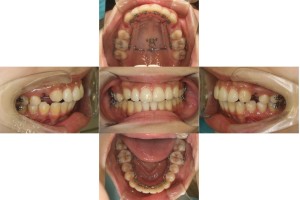

リンガル矯正なので上下裏側に装置を付けさせて頂きました。

上顎に小さなネジ(アンカースクリュー)を埋入し、歯を引っ張る土台(固定源)にして効率的に動かしていきます。

上顎両側4番目の歯を抜歯をして、口元を下げていきます。